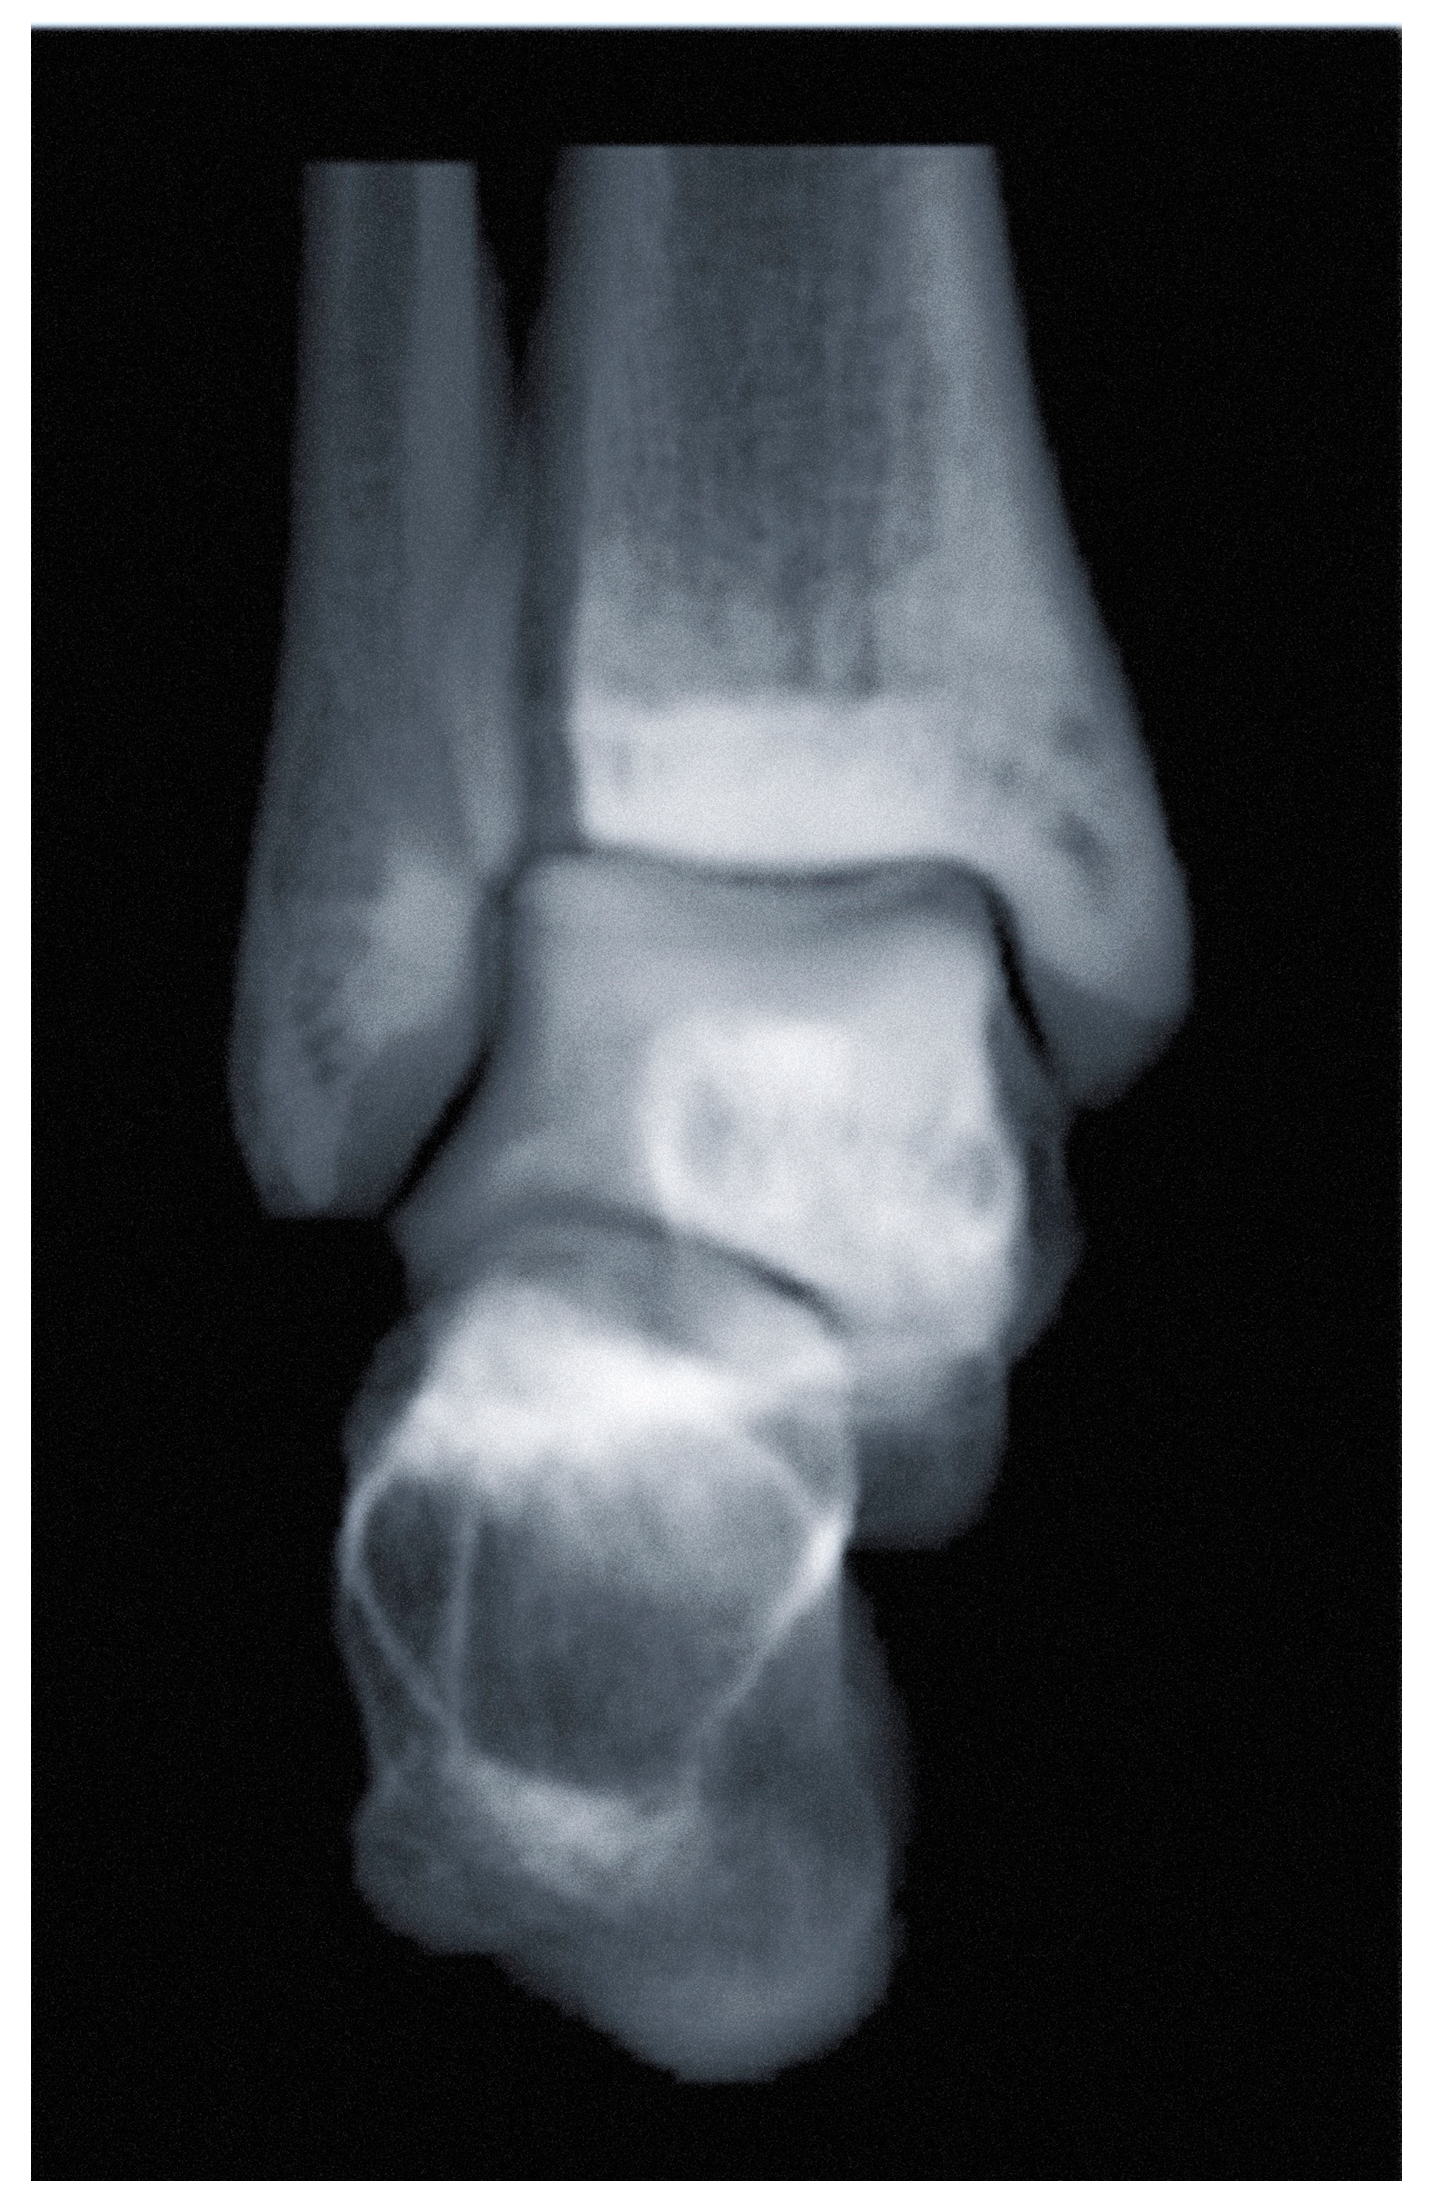

3.1. Ankle Osteoarthritis

3.1.1. Diagnosis

- Tazegul, T.E.; Anderson, D.D.; Barbachan Mansur, N.S.; Kajimura Chinelati, R.M.; Iehl, C.; VandeLune, C.; Ahrenholz, S.; Lalevee, M.; de Cesar Netto, C. An Objective Computational Method to Quantify Ankle Osteoarthritis from Low-Dose Weightbearing Computed Tomography. Foot Ankle Orthop. 2022, 7, 24730114221116805. [Google Scholar] [CrossRef]